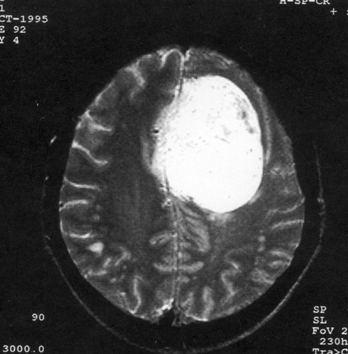

问题 病历摘要:??患者女性,37岁。大便时突起炸裂样头痛3小时,伴喷射样呕吐。既往体健。体检:T37.5℃,BP145/90mmHg,R20次/分,P85次/分。神志清楚,颅神经检查无异常,颈强直,克、布氏征(-),四肢肌力、肌张力正常,病理征(-)。 根据以上情况,可采取哪些处理措施?提示:手术成功夹闭动脉瘤,术后患者恢复可。但术后第?3日患者左肢体肌力渐变差(3级),复查CT未见颅内出血,床边TCD示右颈内动脉血流速度加快。

选项 A.应用尼莫地平 B.脑脊液引流 C.适当提高血压 D.增加输液量 E.应用低分子右旋糖酐 F.使用糖皮质激素 G.应用甘露醇 H.必要时行介入血管成形术

答案 ACDEH